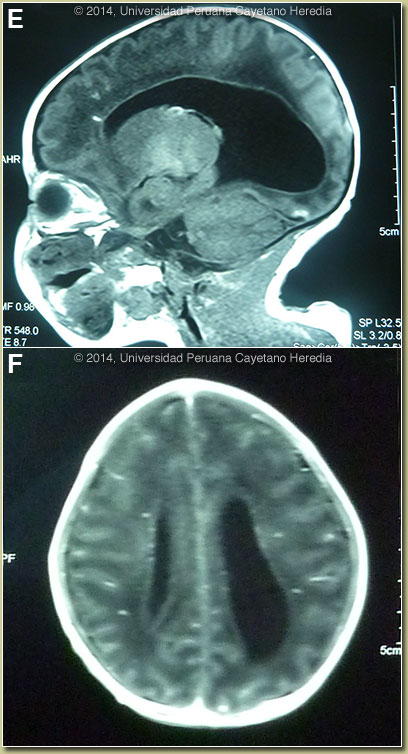

Discussion: A Toxoplasma IgM on the infant’s serum was 3.8 (N<1.1). Testing for HSV1, HSV2, Rubeola, and CMV IgM was negative. Congenital rubella has been eradicated from Perú. The funduscopic examination revealed a normal left eye and the right eye had uveitis with a vitreal reaction and a large cotton wool spot but no retinal scarring. Focal necrotizing retinitis and scarring is only present at birth in 20% and usually occurs later after birth if untreated. The CT scan [Images C & D] was read as showing bilateral enlargement of the lateral ventricles with both periventricular and sub-cortical calcification. An MRI [Images E & F] showed the ventricular dilatation, periventricular leukomalacia, decreased size of the corpus callosum, and there were petechial hemorrhages with foci of hemosiderin deposition [punctate enhancing lesions in Image F]. In retrospect the mother recalled a 1-day flu like illness without fever during the 29th week of gestation for which she did not seek medical care. Testing for CMV, EBV, and rubeola IgG in the mother was positive. Toxoplasma IgG in the mother was 1018 (N<3); no IgM for Toxoplasma was performed.